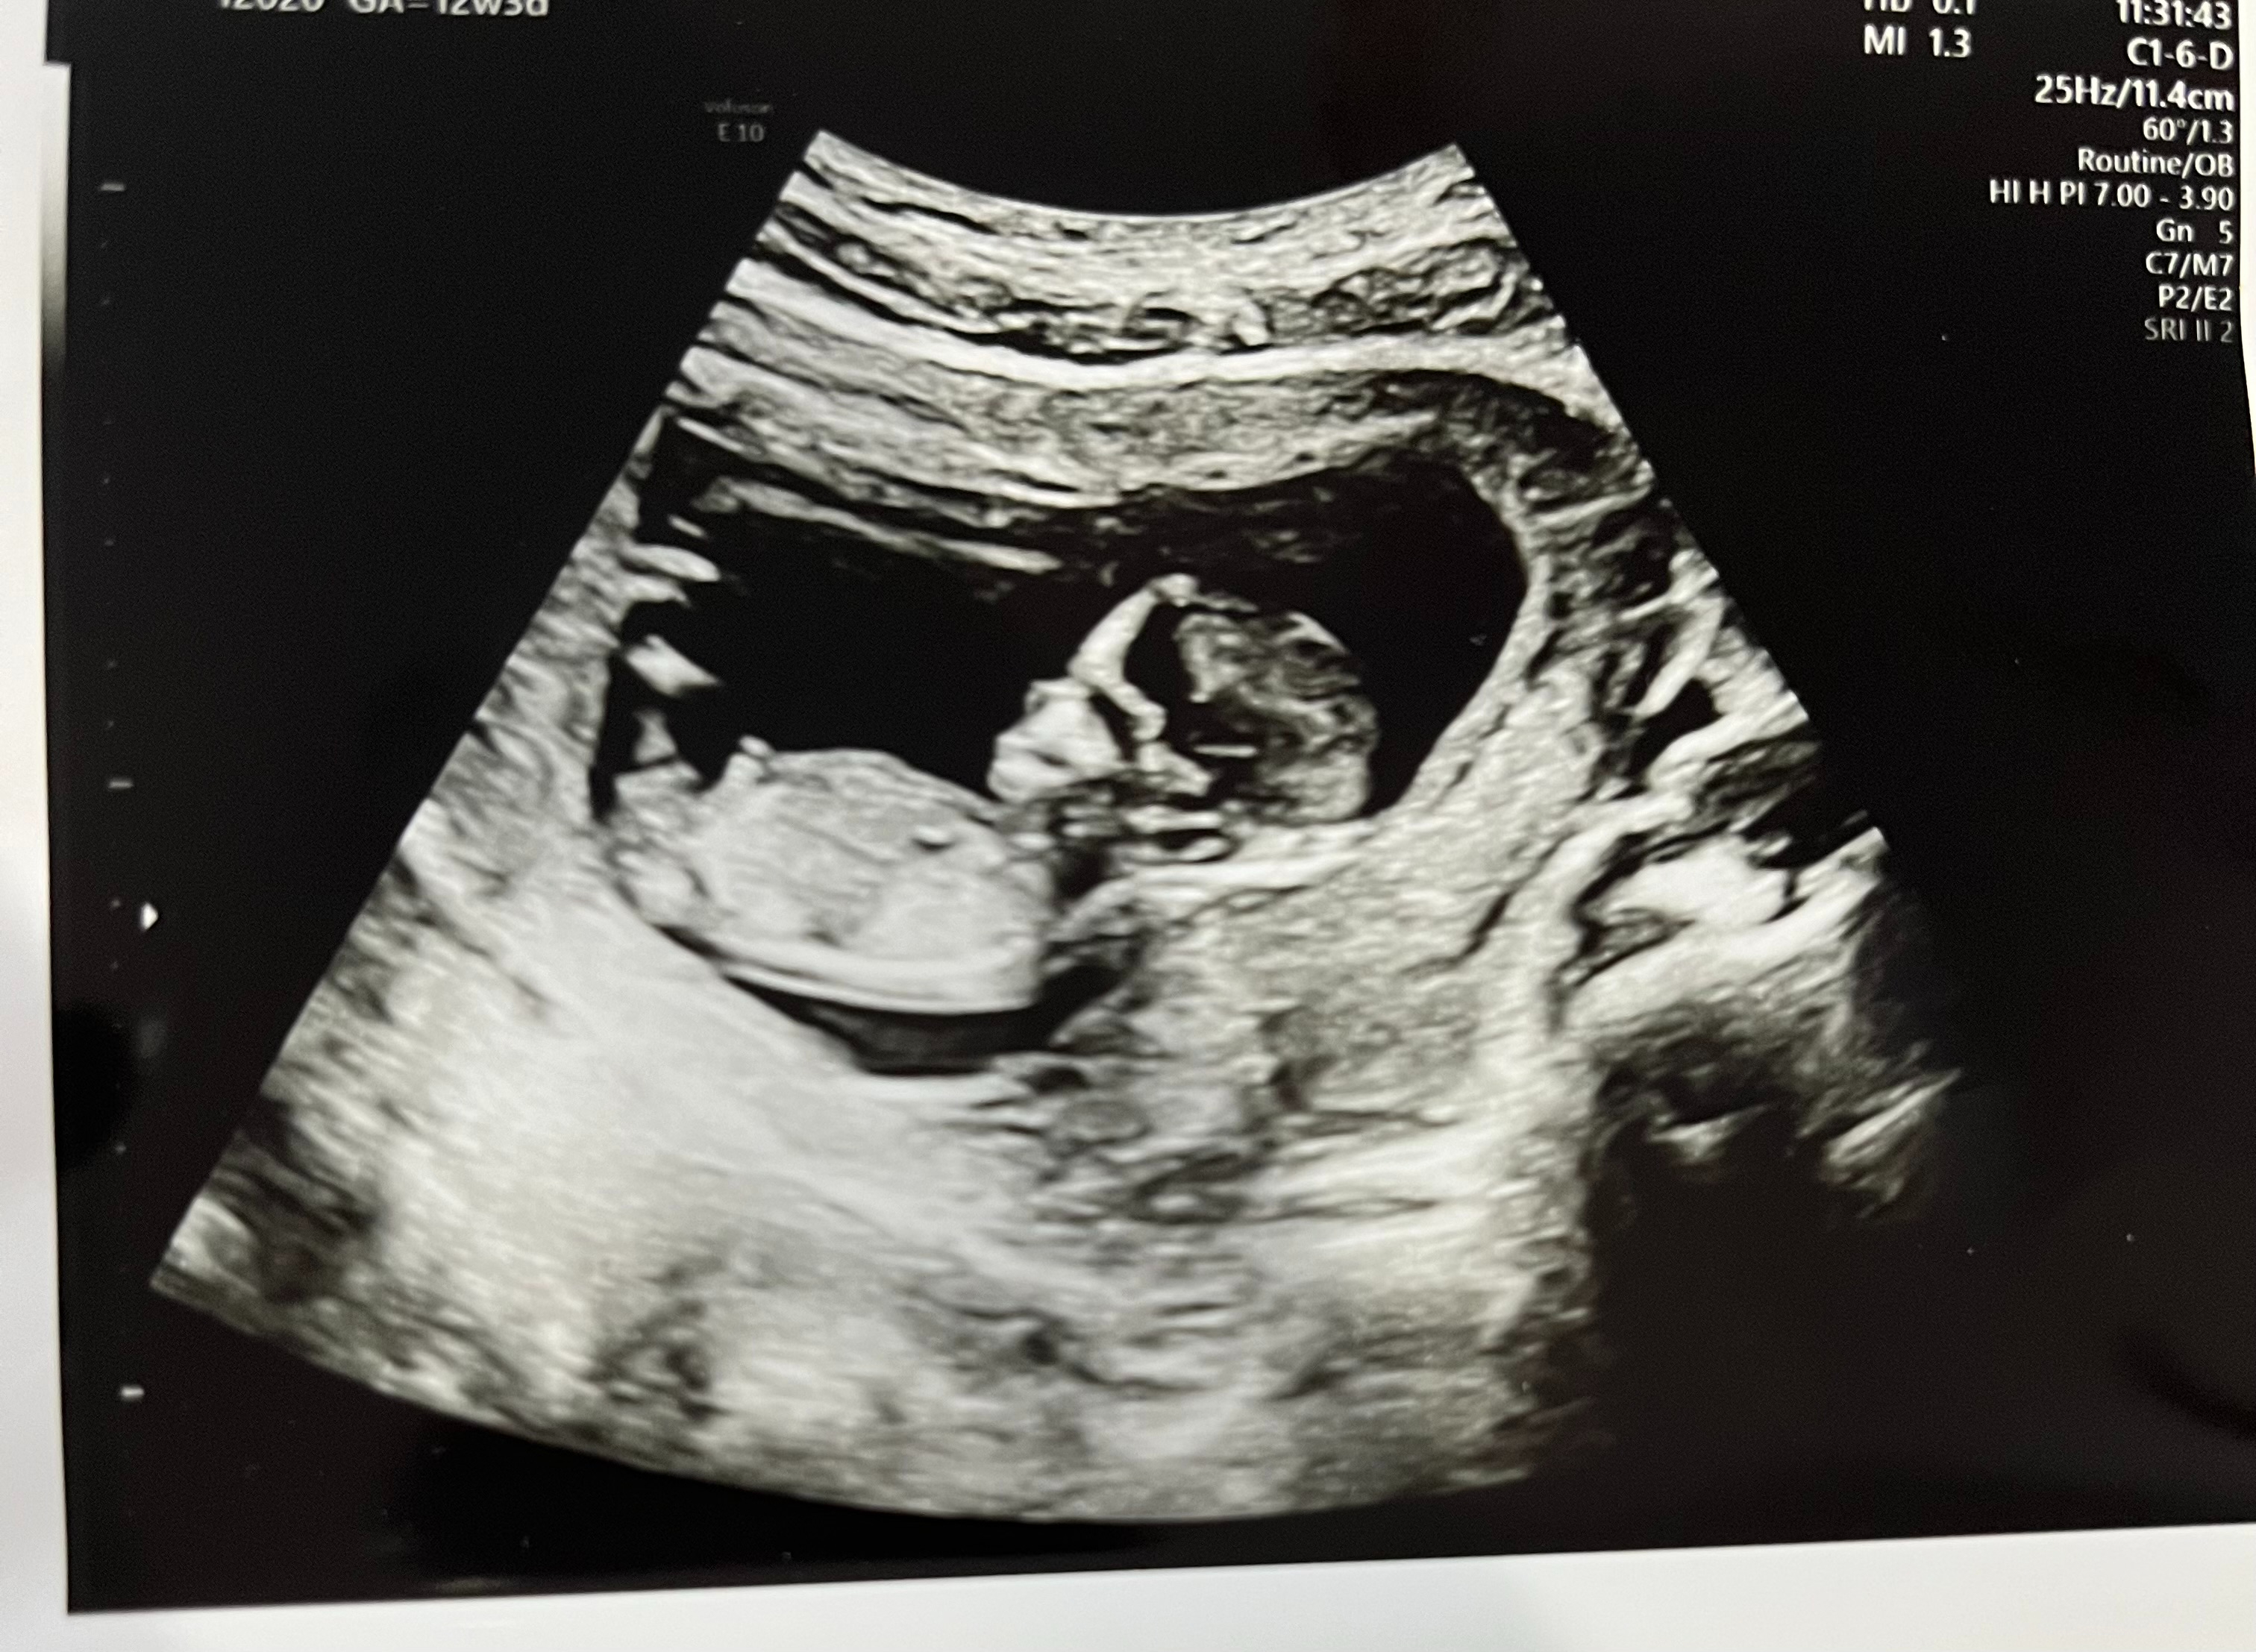

IMG_E4158[1].JPG

この前の健診でのエコーです。

だいぶ人間の形になってきましたね笑

超音波で見てもらってた時、ゴロゴロと動いたり飛び跳ねてる姿が見られました♪愛しさマシマシです!